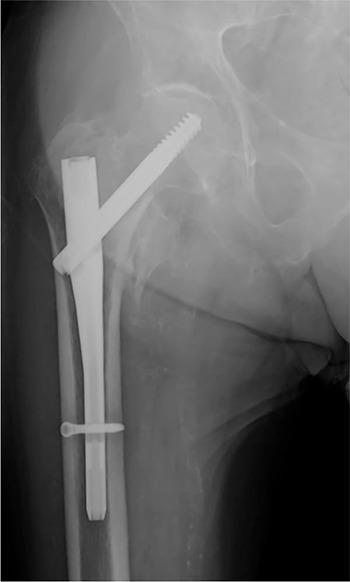

Pertrochanteric hip fractures are among the most common and the use of short cephalomedullary nails as the treatment of choice is increasing.A systematic review regarding distal locking options for short cephalomedullary nails was undertaken using Medline/PubMed®, Embase® and Cochrane Library® in order to evaluate current indications, associated complications and to provide treatment recommendations.The results seem to support the use of distal static locking for unstable fractures, dynamic locking for length stable/rotational unstable fractures and no locking for stable fractures.Complications associated with distal locking include iatrogenic fractures, thigh pain, delayed union and nonunion, implant failure, screw loosening and breaking, drill bit breaking, soft tissue irritation, femoral artery branch injury, intramuscular haematoma and compartment syndrome. It is also associated with longer operative time and radiation exposure.In unlocked constructs, dorsomedial comminution and nail/medullary canal mismatch contribute to peri-implant fractures. Anterior cortical impingement is associated with cut-out and nonunion.Most studies comparing distally locked and unlocked nails report a short follow-up.Distal locking mode should be based on the fracture's stability. Cite this article: 2020;5:421-429. DOI: 10.1302/2058-5241.5.190045.

转子周围髋部骨折是最常见的骨折之一,使用短髓内钉作为首选治疗方法的情况正在增加。我们使用Medline/PubMed®、Embase®和Cochrane图书馆®对短髓内钉的远端锁定选择进行了系统评价,以评估当前的适应证、相关并发症并提供治疗建议。结果似乎支持对不稳定骨折采用远端静态锁定,对长度稳定/旋转不稳定骨折采用动态锁定,对稳定骨折不进行锁定。与远端锁定相关的并发症包括医源性骨折、大腿疼痛、延迟愈合和不愈合、植入物失败、螺钉松动和断裂、钻头断裂、软组织刺激、股动脉分支损伤、肌内血肿和骨筋膜室综合征。它还与更长的手术时间和辐射暴露有关。在非锁定结构中,背内侧粉碎和钉/髓腔不匹配会导致植入物周围骨折。前皮质撞击与穿出和不愈合有关。大多数比较远端锁定和非锁定髓内钉的研究报告的随访时间较短。远端锁定方式应基于骨折的稳定性。引用本文:2020;5:421 - 429。DOI:10.1302/2058 - 5241.5.190045。